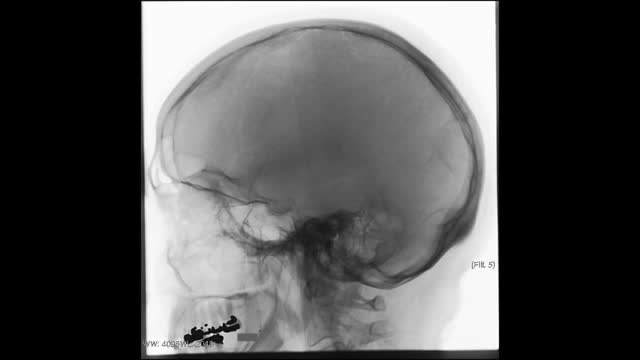

Friedreich's Ataxia

Friedreich's ataxia is an inherited disease that damages your nervous system. The damage affects your spinal cord and the nerves that control muscle movement in your arms and legs. Symptoms usually begin between the ages of 5 and 15. The main symptom is ataxia, which means trouble coordinating movements. Specific symptoms include Difficulty walking Muscle weakness Speech problems Involuntary eye movements Scoliosis (curving of the spine to one side) Heart palpitations, from the heart disease which can happen along with Friedreich's ataxia People with Friedreich's ataxia usually need a wheelchair 15 to 20 years after symptoms first appear. In severe cases, people become incapacitated. There is no cure. You can treat symptoms with medicines, braces, surgery, and physical therapy.